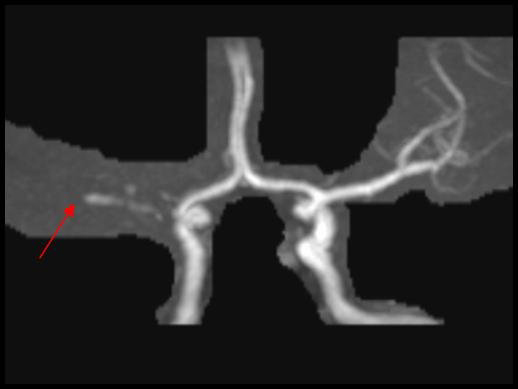

Occlusion de l’artère sylvienne droite

L’angio-IRM montre une occlusion de l’artère sylvienne droite